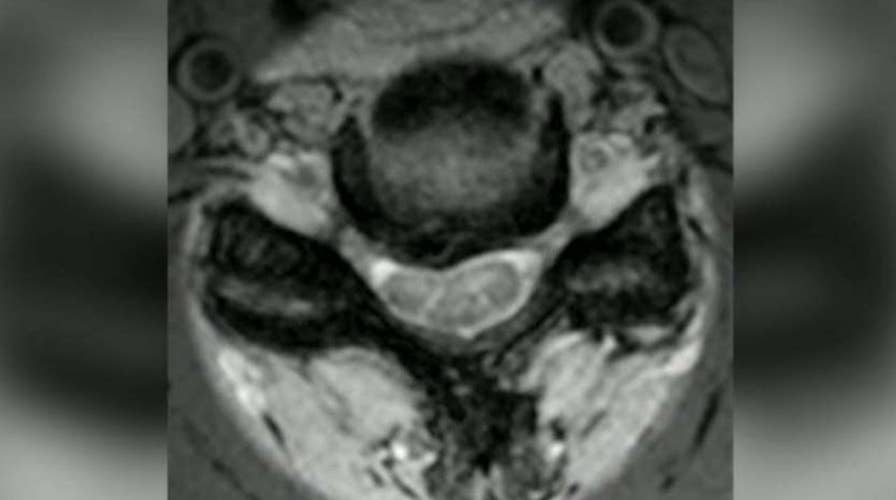

Dr. Marc Siegel explains the surgery Heather Childers will undergo.